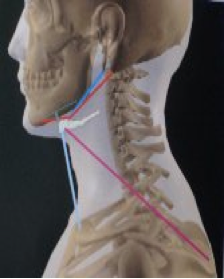

Nella II classe basale avremo: retrusione della mandibola rispetto alla mascella (corrispondente a dislocazione posteriore alta dei condili rispetto alle fosse temporali con conseguenti traiettorie condilari più ripide), lingua interposta anteriormente a riposo e in deglutizione, sigillo labiale inefficiente in quanto il labbro inferiore risulta posteriorizzato rispetto al superiore. Tale situazione si ripercuote sulla postura cervicale e di conseguenza sulla postura in generale. Si potrà, ad esempio, avere prevalenza del tono muscolare posteriore, estensione dell'occipite rispetto all'atlante (la testa "si apre" sul collo), tratto cervicale in rettilinizzazione ma con concentrazione dell'iperlordosi nel segmento atlante-occipite.

Nella III classe avremo: protrusione della mandibola rispetto al mascella (condili in posizione anteriore e inferiore e quindi traiettorie condilari più dolci), lingua in posizione bassa con appoggio sulla mandibola con conseguente incompetenza del sigillo labiale in quanto, in questo caso, il labbro inferiore risulta anteriorizzato rispetto al superiore. In base alle reazioni individuali si potrà, ad esempio, avere una prevalenza della muscolatura anteriore del collo, occipite in flessione rispetto all'atlante (la testa "si ripiega" verso il petto "chiudendosi" sul collo), con alterazione della fisiologica lordosi cervicale che tende a concentrasi nel tratto inferiore per poi rettilinizzarsi o, addirittura, invertirsi nel tratto superiore.